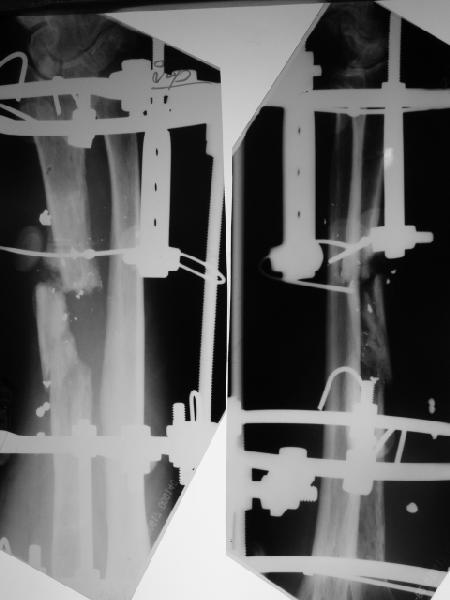

Пока мы наложили аппарат для восстановления оси и длины лучевой кости. Снимок прлагаю.

Спасибо за снимки, один только вопрос-

Снимок сделан после выбирания люфта в аппарате, то есть уже создано приличное дистракционное усилие. Даже пытаться дальше рвать одномоментно не стали.

Спасибо за присланную рентгенограмму после операции. На мой взгляд, было бы неплохо провести еще одну или даже две спицы с упором через промежуточный отломок с противоположной к введенной через дистальный отломок спице с упором.